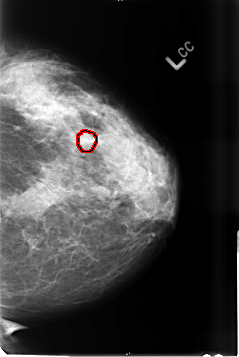

B_3456_1.LEFT_CC

LEFT_CC LINES 4640 PIXELS_PER_LINE 3096 BITS_PER_PIXEL 12 RESOLUTION 50 OVERLAY

FILE: B_3456_1.LEFT_CC.OVERLAY

TOTAL_ABNORMALITIES 1

ABNORMALITY 1

LESION_TYPE CALCIFICATION TYPE PLEOMORPHIC DISTRIBUTION CLUSTERED

ASSESSMENT 4

SUBTLETY 3

PATHOLOGY BENIGN

TOTAL_OUTLINES 1

BOUNDARY